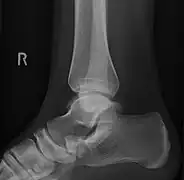

From left to right: Type 1, 2 and 3

Lateral projection of type 2